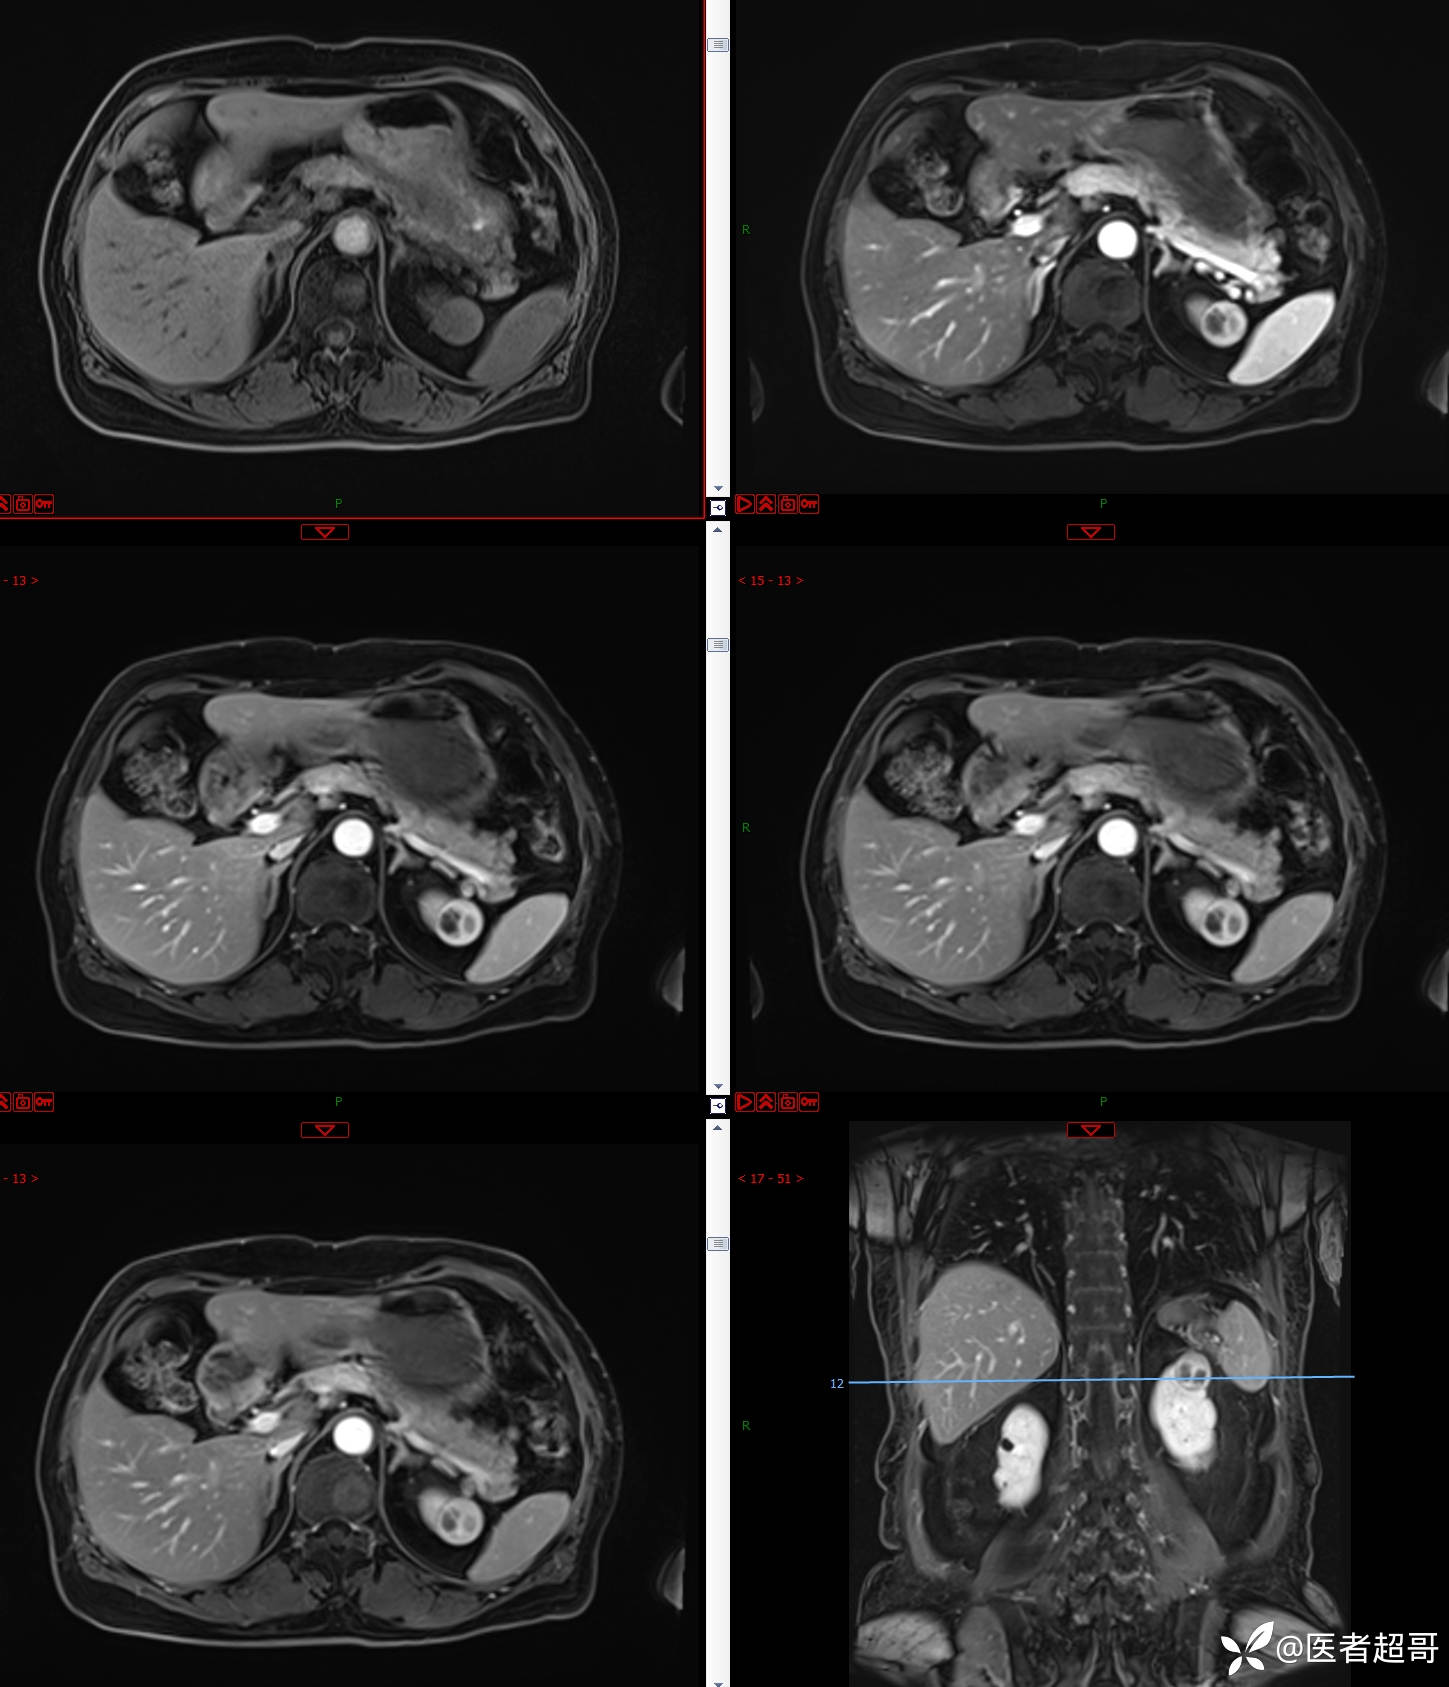

左肾占位2个月就诊,有病理,请分析!

患者 女 73岁

主 诉:查体发现左肾占位2月。

现病史:患者自述2月前于镇中心卫生院行腹部超声发现:左肾实性占位。患者无尿频尿急尿痛,无发热寒战,无恶心呕吐。未行特殊治疗。现患者为求进一步诊治,就诊我院,门诊以“肾肿物”为诊断收入院,患者自发病以来,神志清,精神可,饮食可,睡眠一般,大便正常,体重未见明显改变。